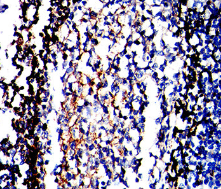

FCM    1/200 - 1/400